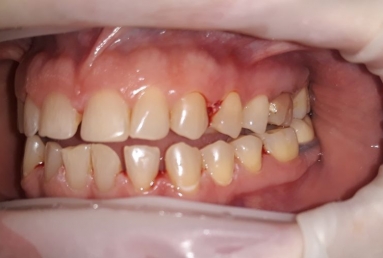

orthodontic treatment, full ceramic crowns

Our patient had general dental abrasion due to maloclusion. After orthodontic treatment, the upper teeth received full ceramic crowns, while the lower were restored with crowns and veneers.